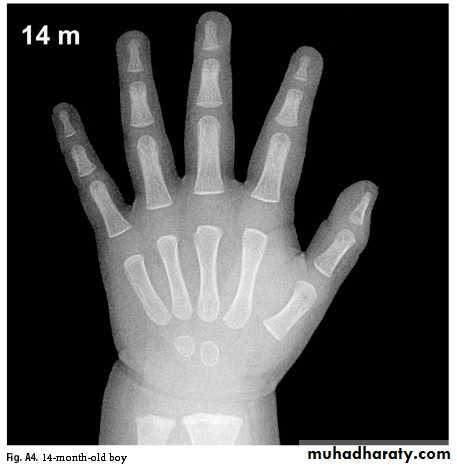

Bone Age

Greulich & Pyle: Radiographic Atlas of Skeletal Development of the Hand and Wrist, This method involves a complex comparison of all the bones in the hand and wrist against reference radiographs of different ages.

Delay of 2 years or more in bone age is significant.